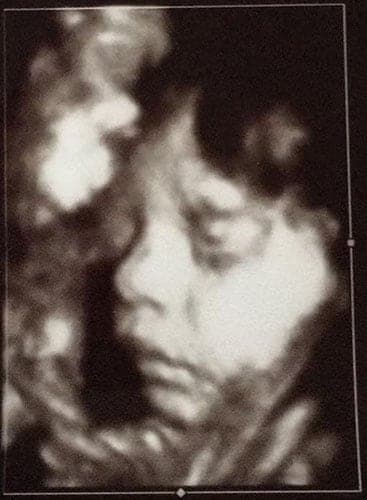

Ultraschallbilder aus dem 3. Trimester (29. bis 40. SSW)

Im dritten Trimester der Schwangerschaft ist das Baby so groß, dass es nicht mehr komplett auf ein Ultraschallbild passt. Nun kann man wunderbare 3D-Ultraschalle des Gesichts machen. In diesem Semester nehmen die Babys nochmal rasant zu und wer Glück hat, kann auf seinem Ultraschall schon erste Gesichtszüge erkennen.

Wer sich jedoch erhofft Gesichtszüge zu erkennen, der wird oft enttäuscht. Zwar kann man beim 3D-Ultraschall schon eine Menge sehen, aber das umgebende Fruchtwasser sorgt in den allermeisten Fällen für starke Störungen.